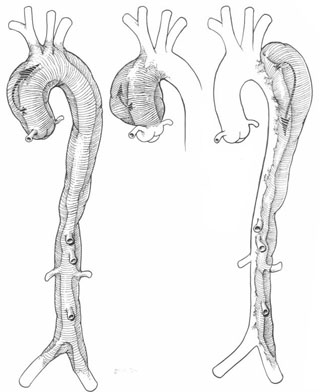

Yerleşimlerine göre aort diseksiyonu tipleri